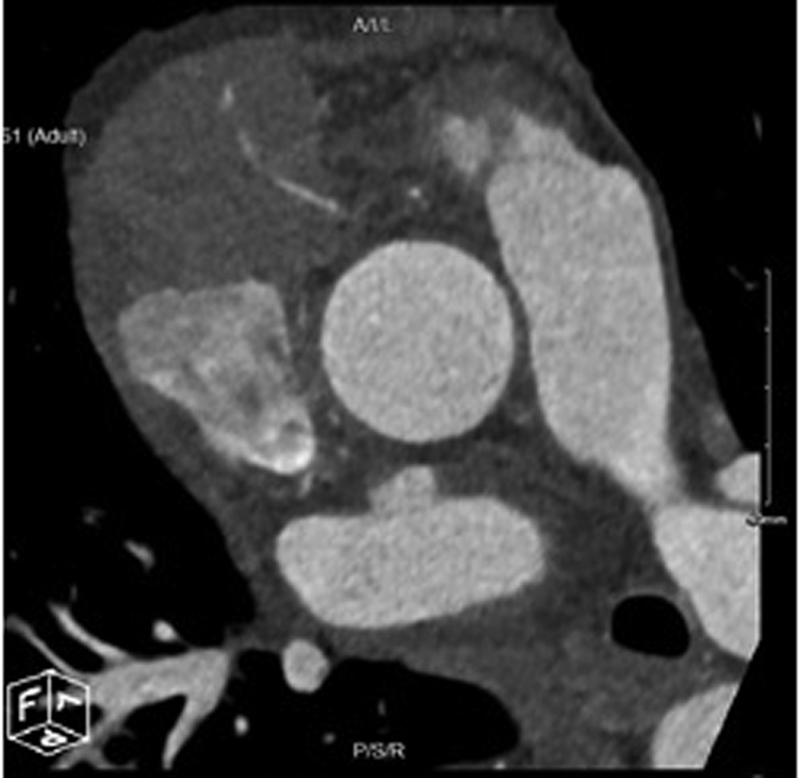

Background  Patients with primary cardiac tumors may present with symptoms based on the size and location of the tumor. Symptoms may include congestive heart failure secondary to intracardiac obstruction, systemic embolization, arrhythmias, and constitutional symptoms. Case Description  A patient presented with new onset atrial fibrillation and heart failure. Workup including open surgery revealed a primary cardiac lymphoma. Conclusion  Cardiac tumors present with a variety of symptoms and are best evaluated by echocardiogram, computed tomography angiography, and magnetic resonance imaging. Tissue diagnosis is necessary. Although primary cardiac lymphoma is rare, long-term survival after chemotherapy and rituximab is superior to other cardiac malignancies.